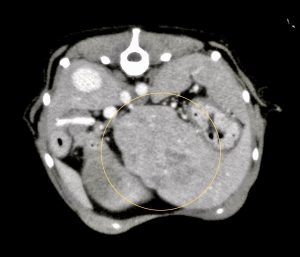

今回治療させていただいたワンちゃんは、数ヶ月前から肝臓(尾状葉乳頭突起)の腫れを指摘されており、CT検査で尾状葉乳頭突起に4センチ大の腫瘤性病変と胃の圧迫、重度の胆嚢拡張を認めました。肝臓腫瘍の初期はほとんど症状がなく(稀に低血糖)、腫瘍が大きくなることで他の臓器を圧迫して症状が出ることが多い印象です。

黄線:肝臓腫瘤

赤矢印:圧迫された胃